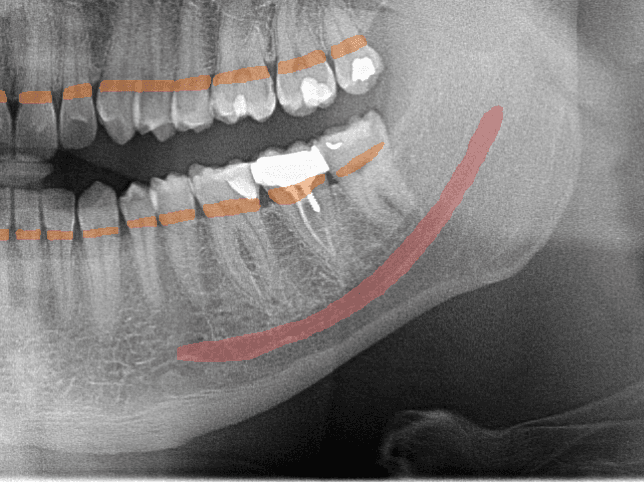

01Anatomy DetectionMay mark IAN canal, mental foramen, maxillary sinus boundaries, and root apices for clinician review

02Bone SegmentationMay support clinician review of bone levels and possible horizontal or vertical defect patterns

Periapical LesionRoot ResorptionRoot FractureShort Root Canal FillingOverfilled CanalPeriapical AbscessInternal ResorptionPulp Stone

Periapical (PA)Candidate periapical, root, caries-depth, and endodontic observations at tooth level